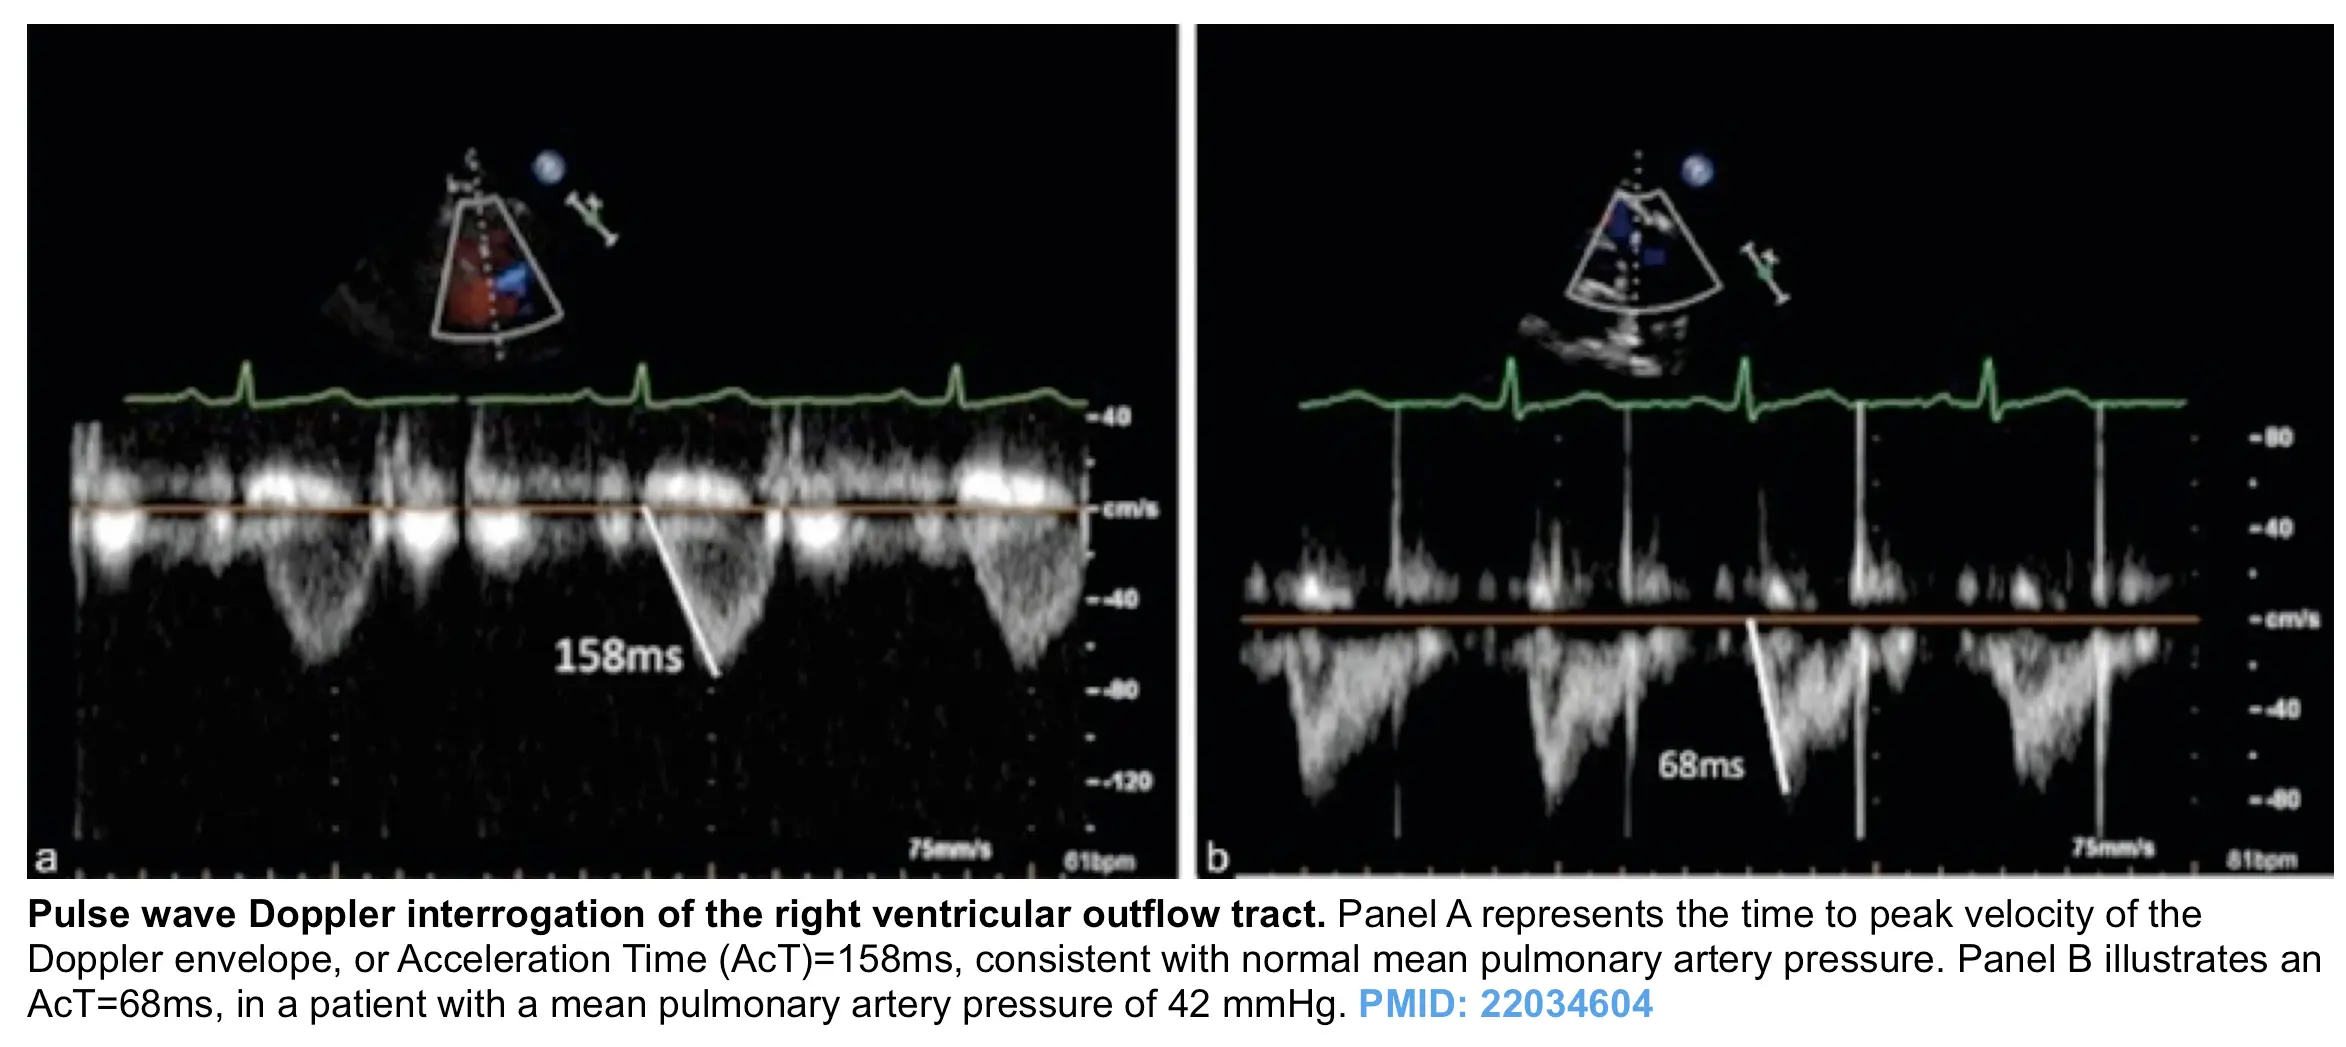

• In healthy adults, a normal PV acceleration time is >110 ms.

• If <105 ms or evidence of systolic notching (figure on right below), may indicate elevated PASP.

• When PVAT <90 ms, can identify most patients with PVR ≥ 3 WU (See Pulmonary Hypertension)